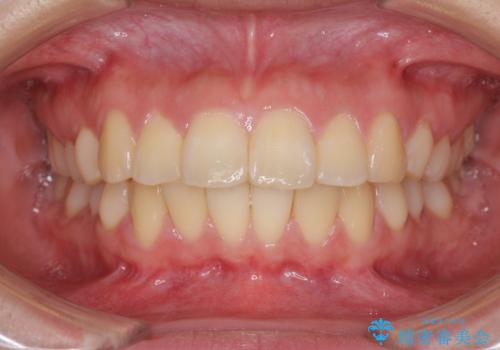

部分矯正で出っ歯になった 出っ歯改善の抜歯矯正

- 上下前歯を部分矯正したところ出っ歯になってしまったとのことで来院された患者様です。

上下左右第一小臼歯4本を抜歯して、積極的に口元を引っ込めるよう、ワイヤー装置にて矯正治療を行うこととしました。

治療後には口が閉じやすくなり、患者様には大変満足していただきました。